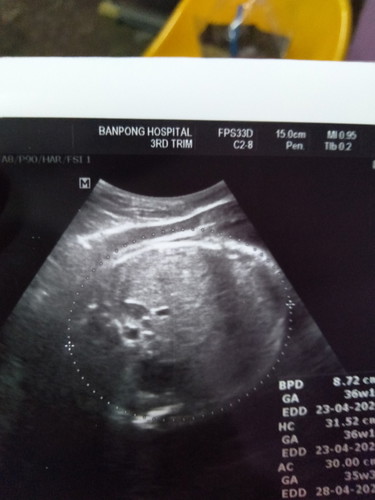

35+4

น่าจะเป็นส่วนกระโหลกหัวหรือเปล่าค่ะ ตอนหมอซาวให้หมอก็แจ้งนะค่ะ ทางการแพทย์เขาเรียกว่า เส้นวัดรอบศีรษะ

ไม่แน่ใจว่าส่วนใหน แต่เป็นภาพตัดขวาง ไม่น่าจะเห็นจมูกน้องค่ะแม่

หมอทำกลมๆครอบเหมือนจะเป็นช่วงศรีษะเลยค่ะ

เป็นช่วงลำตัว ส่วนของช่องท้องค่ะ